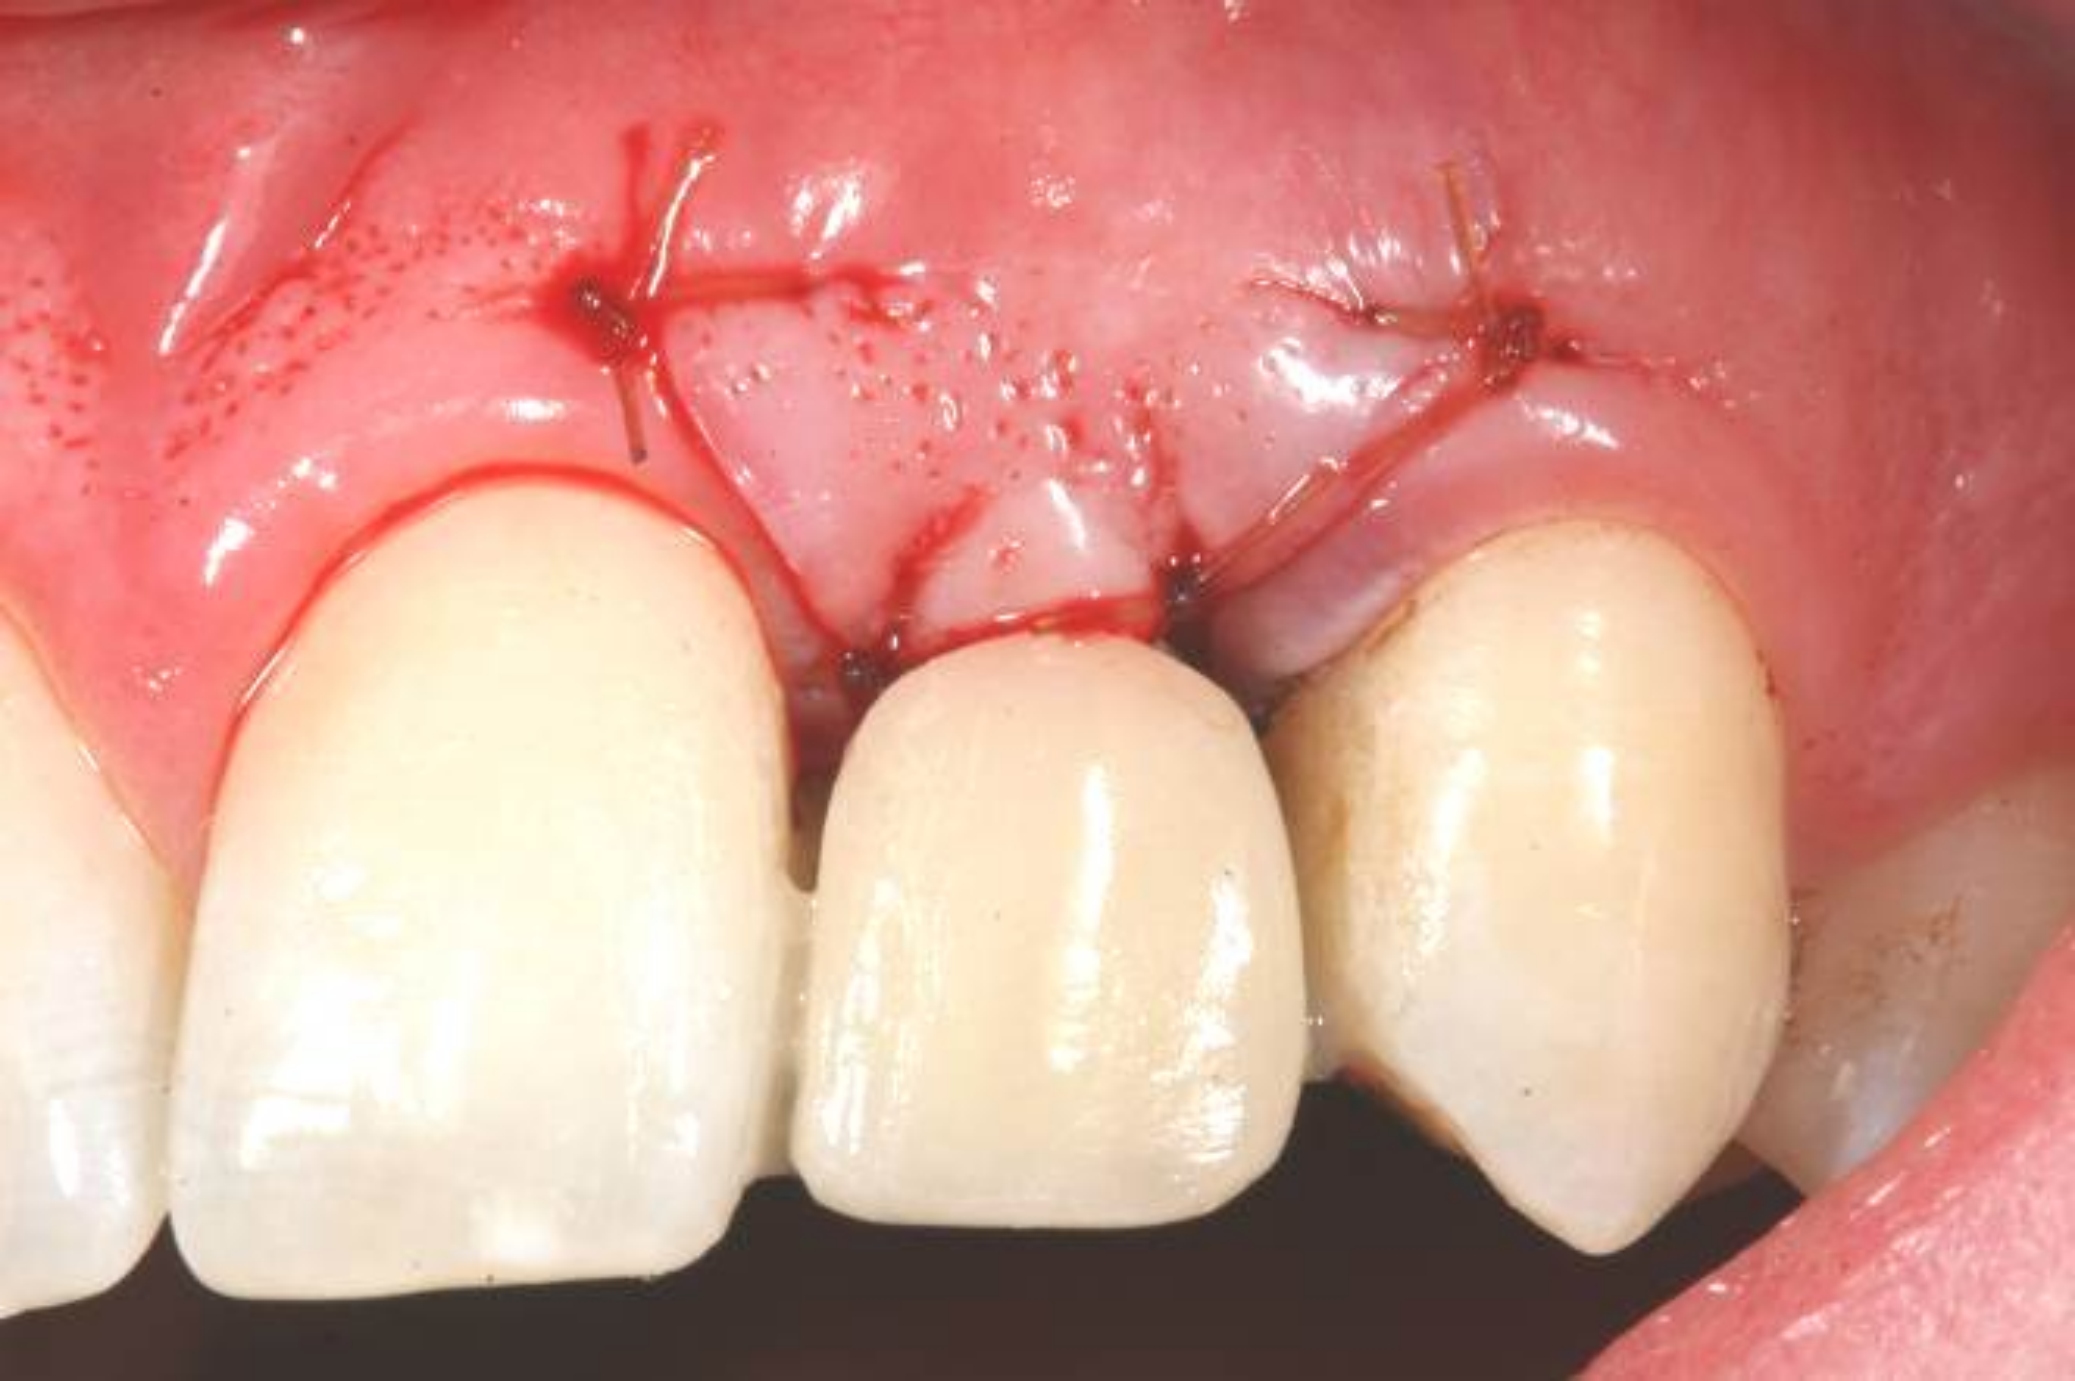

Fig 7. Vertical releasing incisions sutured to attain primary closure, buccal view.

Figure 7

Fig 8. Submerged implant protocol, occlusal view. A horizontal releasing incision was sutured to attain primary closure. Note that there are no sutures through the thin retained papillary segments.

Figure 8

In the esthetic zone it is preferable to avoid elevating papillae because flap elevation may induce recession and create unesthetic black triangles.4 If a flap is necessary to perform a procedure in an edentate area when adjacent teeth are present, the following technique can be used to circumvent blunting papillae. Make a horizontal incision along the midcrestal or palatal aspect of the ridge and terminate the incision 1 mm from the adjacent teeth (Figure 1). The incision is created palatally if it is desired to transpose keratinized tissue to the buccal. From the horizontal incision, create bilateral buccal vertical releasing incisions that extend obliquely at an angle (Figure 2). The vertical incisions can also be extended palatally (for access), but this is not always necessary (Figure 3). Preserved papillae contain gingival supracrestal fibers that subsequently help maintain papillary height (Figure 4). The distance the incision is extended vertically on the buccal is dictated by the task to be accomplished (eg, implant insertion only requires short vertical incisions, while bone grafting needs longer incisions) (Figure 5 and Figure 6). At the end of the surgical procedure, the severed papillary segments are sutured to their retained counterparts (Figure 7 and Figure 8). Figure 1 through Figure 8 demonstrate a submerged implant protocol.